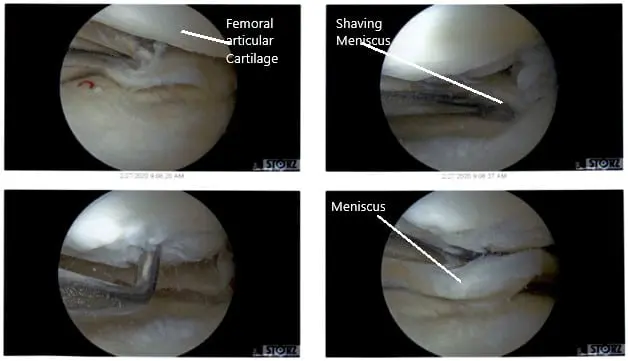

There were some medial margin tearing and fraying of the lateral meniscus which was taken care of with the shaver and meniscectomy performed to stable margins. The ACL (history of ACL reconstruction) showed fraying in the intertrochlear notch, but the ACL was intact.

Debridement of the ACL was performed. Clean up of the meniscocapsular junction of the medial meniscus was performed. The rasping of the meniscus as well as the capsule was performed in preparation for the repair using a shaver and arthroscopic rasps. Chondroplasty of the medial femoral condyle, trochlea, patellar lateral facet was performed. Decisional for repair was undertaken.

Intraoperative Arthroscopic Views of the left knee.